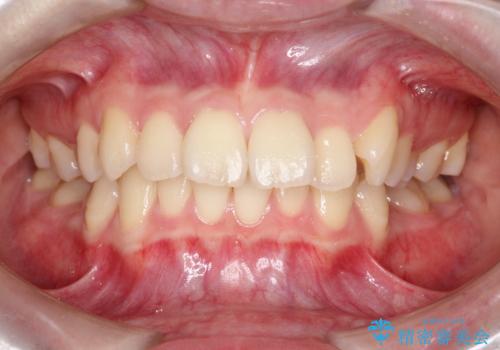

前歯の突出と下顎の偏位を改善。審美ワイヤーで整えるバランスの良い歯並び